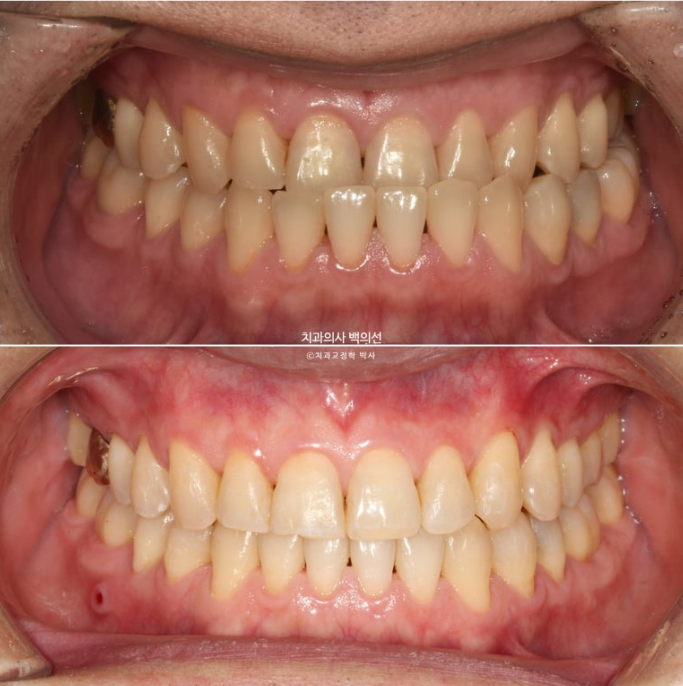

23년 12월 주걱턱 치료를 위해 오신 40대 환자분입니다.

골격적 주걱턱 뿐만 아니라 아래턱이 왼쪽으로 틀어진 비대칭도 보입니다.

23.12

앞니가 완전히 거꾸로 물립니다.

치료 전 후 비교 보겠습니다.

23.12~25.03